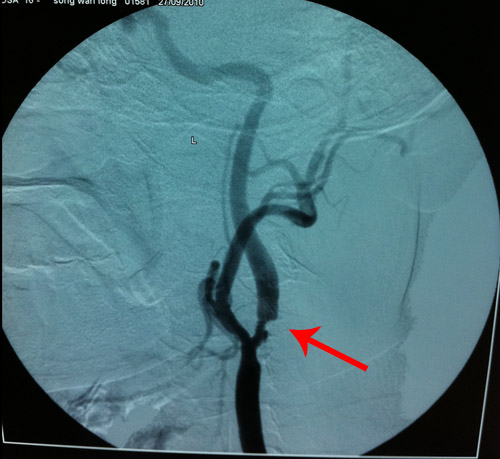

DSA示:右侧颈总动脉远端,右侧颈内动脉起始处,右侧颈外动脉起始处有粥样斑块形成,狭窄;左侧颈总动脉远端,左侧颈内动脉起始处粥样斑块形成,狭窄。

箭头所示为左侧颈动脉狭窄处